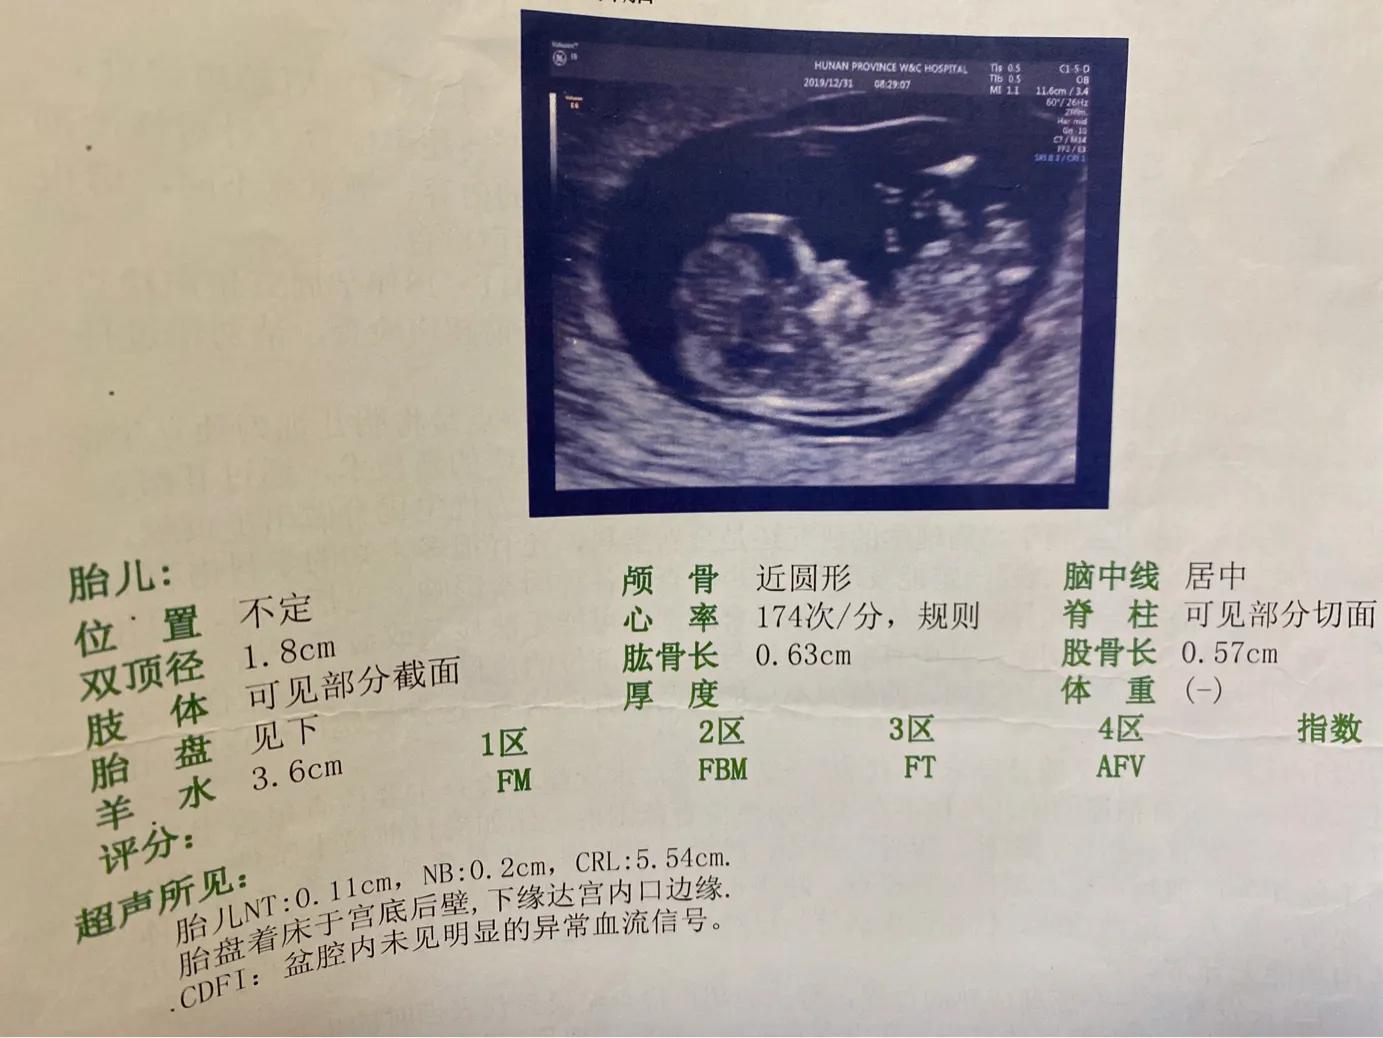

划重点:第一次大检查,医生会开两个大的项目,一个是血液检查(我抽了13管血)还有一个是四维也就是NT (省妇幼所有的四维都要提前预约,不能当天做),还有就是尿检和心电图,医生都会建议四维做,因为怕宝宝有畸形啥的(畸形的话医生会建议RL ),没有问题在进行抽血大检查,我建议是一般孕妇宝宝都没有大的问题,当天看医生,如果没有吃早饭的话,可以把抽血先做了,然后让医生开好四维的单子,到五楼进行预约,预约号下次直接来做检查,这样的话就免得多跑一次,因为血液检查好几个项目是三个工作日以后出结果,所以提前做完血液检查等到检查四维的时候就可以一起把所有的检查单拿给医生看,就免得再跑一趟,陪护的准爸爸准妈妈如果是自由职业还好,一般情况下就又得向领导请假了。